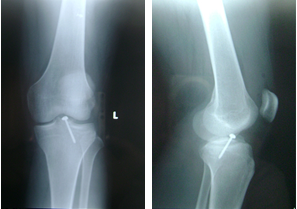

术中探查见骨折复位良好,固定可靠,前交叉韧带走形正常,张力好,行前抽屉试验可见膝关节稳定。术后X线可见骨折复位良好,内固定螺钉及垫片位置合适、牢固(如图3所示)。本组病例均得到随访,随访时间6-18个月,平均11个月,了解骨折愈合情况以及膝关节功能恢复情况。应用Lysholm膝关节功能评分法,对疼痛、肿胀、行走功能等内容进行评分。结果显示术后6个月,本组病例结果优29例,良7例,可3例,优良率为92.3%。

图3 前交叉韧带胫骨止点撕脱骨折术后